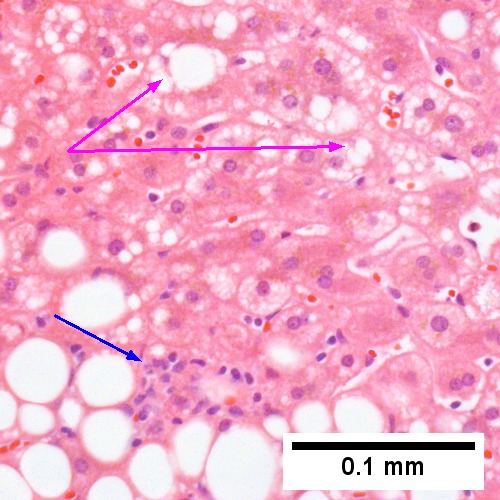

B. Ballooning degeneration, with cytoplasmic tufts (arrows) (400X).

Steatohepatitis Brunt necroinflammatory grade 3, Brunt fibrosis stage 1. A. Panacinar steatosis with unremarkable, small triads. B. Ballooning degeneration, with cytoplasmic tufts [arrows]. C. Lipogranuloma. D. Triad with mild chronic inflammation without interface hepatitis.

C. Cytoplasmic tufts (arrows) prove ballooning degeneration (Row 2 Left 400X).

Steatohepatitis. Brunt necroinflammatory grade 3, Brunt fibrosis stage 3. A. Steatosis afflicts almost all hepatocytes (pan-acinar). B. An isolated septal duct with concentric fibrosis [arrow] should not result in a diagnosis of primary sclerosing cholangitis. The woman who underwent the biopsy had a normal bilirubin level, a normal alkaline phosphatase level, and only slightly elevated transaminase levels. C. Cytoplasmic tufts [arrows] prove ballooning degeneration. D. PAS with diastase shows PAS-D Kupffer cells (arrows). E. Reticulin shows thick black lines [red arrows] of collapse, without portal central bridging. The apparent loss of reticulin due to steatosis [double head cyan arrow] should not be considered regeneration or hepatoma. F. Trichrome shows a bridge [arrow].

Steatohepatitis. Brunt necroinflammatory grade 2. Brunt fibrosis stage 2. A. Steatosis is not pan-acinar, precluding grade 3. B. Cytoplasmic tufts [arrows] were commonly seen establishing frequent ballooning degeneration of grade 2. C. Trichrome shows periportal fibrosis [arrow] establishing fibrosis stage 2. D. PAS D shows a triad with mild damage, with an interlobular bile duct [green arrow] with luminal sheered epithelium, not neutrophils, a hepatic arteriole [red arrow], a hepatic venule [blue arrow], proliferating bile ductules [cyan arrows]; PAS-D macrophages [black arrows] in triad & sinusoid evidence damage; Neutrophils [magenta arrows] in proliferating bile ductules mean nothing, but in sinusoids indicate damage. E. Reticulin fibers in steatosis afflicted areas can appear abnormally lost, which should not be deemed evidence of hepatocellular carcinoma. F. Reticulin stain here shows hepatocyte acini [arrows], evidence of hepatocellular injury (Row 3 Right 400X).

Steatohepatitis. Brunt necroinflammatory grade 1. Brunt fibrosis stage 1. A. Steatosis afflicts about 30% of hepatocytes; note the absence of visible triads. B. Cytoplasmic tufts of ballooning degeneration [violet arrows] were commonly found; a lymphohistiocytic aggregate [blue arrow], important for NAFLD, but not for Brunt, is seen. C. A triad shows a vein [green arrow], an artery [red arrow], an interlobular duct [blue arrow], and proliferating bile ductules [cyan arrows]; only a few lymphocytes are seen . D. Central vein shows only a few endothelial cells, with somewhat packed hepatocytes surrounding it. E. Trichrome shows mostly space of Disse fibrosis [black arrows], sometimes adjoining hepatocytes [green arrows] show this is a stage 1 fibrosis. F. Trichrome shows a central vein with a minimum of sclerosis; an interhepatocyte fibrous extension [arrow] displays the very beginning of fibrosis.